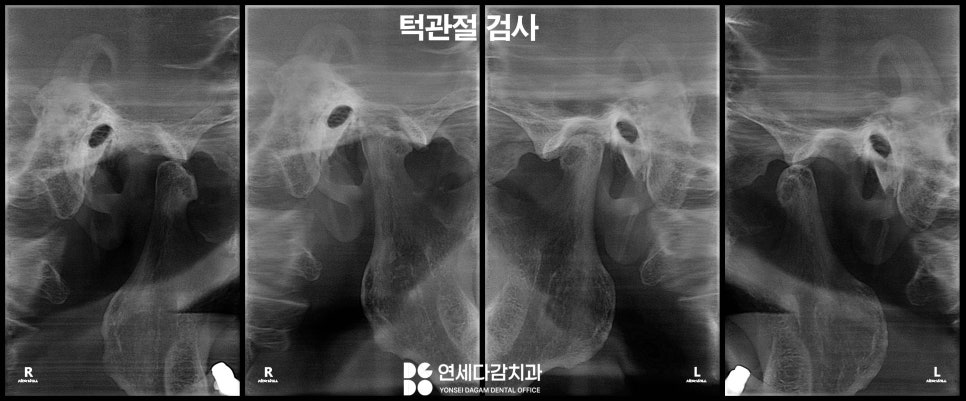

충치, 잇몸 질환, 턱관절 장애 등이

턱관절이나 씹는 근육인

교근과 측두근에도 이상이 없다면